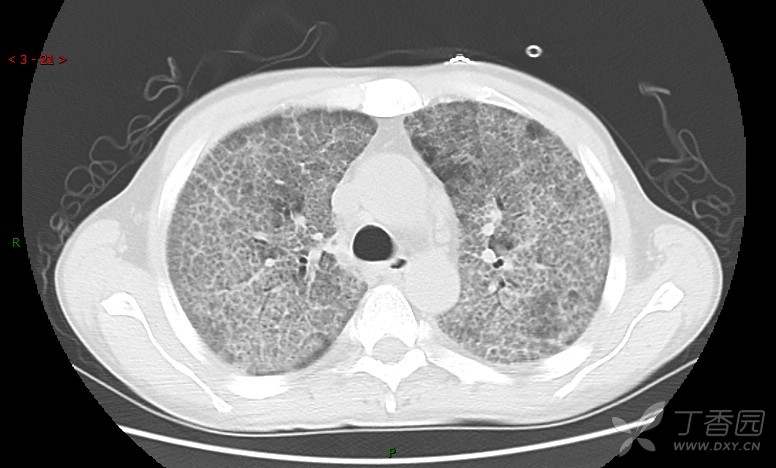

地图+铺路石征=PAP?那升高的CEA怎么说(病例3连发,附其他2例链接)

患者男,42岁,咳嗽半年余,加重伴憋喘2月余。

患者半年余前无明显诱因出现间断咳嗽,干咳为主,偶咳少量黄白痰,剧烈咳嗽或运动后可出现轻度憋喘,无高热、脓臭痰,无胸痛、咯血及晕厥,无低热乏力及盗汗,无心前区压榨感及夜间阵发性呼吸困难,初未在意,未予正规诊治。2月余前患者自觉上述症状较前加重,咳嗽、憋喘明显,黄白色粘痰略有增多,伴有发热,热前伴有畏寒、寒战,体温最高达38.9℃,先后就诊多家医院,入住重症监护室,未行气管插管,考虑“重症肺炎”,给予“美罗培南、复方磺胺甲噁唑”等药物抗感染,“卡泊芬净”抗真菌,并给予“甲泼尼龙”等药物治疗35天,经治疗后症状好转于2018-04-02出院。患者自出院后仅应用中药治疗(具体不详),并给予家庭氧疗,平素仍有间断咳嗽,咳少量黄白色粘痰,活动后憋喘明显,活动耐量差,以卧床为主。

肺内弥漫性网状结节影,PET-CT却无阳性病灶,这是?(附其他2例链接)